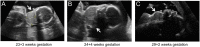

In the absence of maternal thyroid disease or iodine deficiency, fetal goitre is rare and usually attributable to dyshormonogenesis, for which genetic ascertainment is not always undertaken in the UK. Mechanical complications include tracheal and oesophageal compression with resultant polyhydramnios, malpresentation at delivery and neonatal respiratory distress. We report an Indian kindred in which the proband (first-born son) had congenital hypothyroidism (CH) without obvious neonatal goitre. His mother's second pregnancy was complicated by fetal hypothyroid goitre and polyhydramnios, prompting amniotic fluid drainage and intraamniotic therapy (with liothyronine, T3 and levothyroxine, T4). Sadly, intrauterine death occurred at 31 weeks. Genetic studies in the proband demonstrated compound heterozygous novel (c.5178delT, p.A1727Hfs*26) and previously described (c.7123G > A, p.G2375R) thyroglobulin (TG) mutations which are the likely cause of fetal goitre in the deceased sibling. TG mutations rarely cause fetal goitre, and management remains controversial due to the potential complications of intrauterine therapy however an amelioration in goitre size may be achieved with intraamniotic T4, and intraamniotic T3/T4 combination has achieved a favourable outcome in one case. A conservative approach, with surveillance, elective delivery and commencement of levothyroxine neonatally may also be justified, although intubation may be required post delivery for respiratory obstruction. Our observations highlight the lethality which may be associated with fetal goitre. Additionally, although this complication may recur in successive pregnancies, our case highlights the possibility of discordance for fetal goitre in siblings harbouring the same dyshormonogenesis-associated genetic mutations. Genetic ascertainment may facilitate prenatal diagnosis and assist management in familial cases.

Learning points: CH due to biallelic, loss-of-function TG mutations is well-described and readily treatable in childhood however mechanical complications from associated fetal goitre may include polyhydramnios, neonatal respiratory compromise and neck hyperextension with dystocia complicating delivery.CH due to TG mutations may manifest with variable phenotypes, even within the same kindred.Treatment options for hypothyroid dyshormogenic fetal goitre in a euthyroid mother include intraamniotic thyroid hormone replacement in cases with polyhydramnios or significant tracheal obstruction. Alternatively, cases may be managed conservatively with radiological surveillance, elective delivery and neonatal levothyroxine treatment, although intubation and ventilation may be required to support neonatal respiratory compromise.Genetic ascertainment in such kindreds may enable prenatal diagnosis and anticipatory planning for antenatal management of further affected offspring.